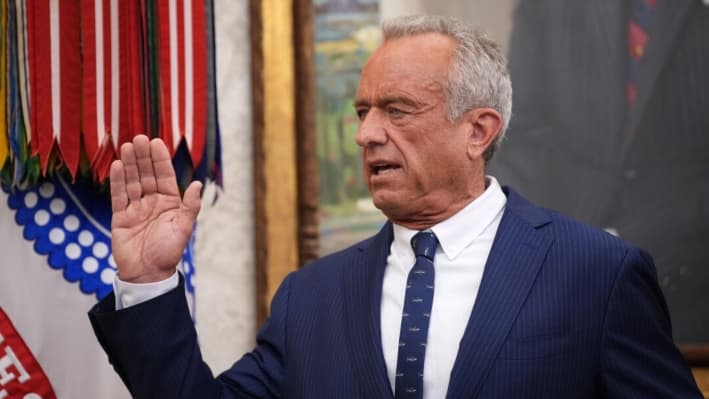

Director interino de los CDC pide a los fabricantes que distribuyan la vacuna MMR en dosis separadas

Cómo podría cambiar el calendario de vacunación infantil bajo la directiva de Trump

¿Qué está pasando realmente con la política de vacunación?

Estamos asistiendo al surgimiento de la elección y el voluntariado como elementos primordiales, tal y como debió ser desde el principio.